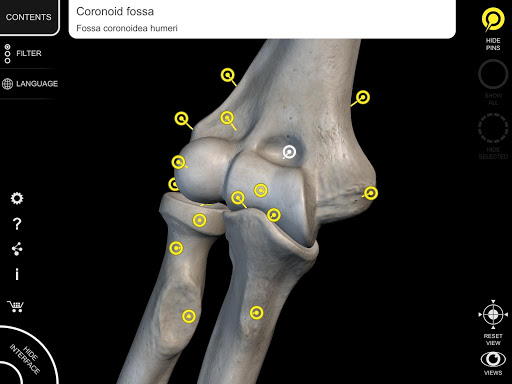

Mỗi xương của bộ xương người đã được tái tạo ở dạng 3D, bạn có thể xoay và phóng to từng mô hình và quan sát chi tiết từ mọi góc độ.

Bằng cách chọn mô hình hoặc ghim, bạn sẽ được hiển thị các thuật ngữ liên quan đến bất kỳ bộ phận giải phẫu cụ thể nào, bạn có thể chọn từ 12 ngôn ngữ và hiển thị các thuật ngữ bằng hai ngôn ngữ cùng lúc.

HÌNH GIẢI PHẪU 3D CÓ ĐỘ CHI TIẾT CAO

• Hệ thống xương

• Mô hình 3D chính xác

• Bề mặt của bộ xương có kết cấu độ phân giải cao lên đến 4K

• Phân chia theo vùng để có hình ảnh rõ ràng và trực tiếp về từng cấu trúc

• Ghim tương tác cho phép trực quan hóa thuật ngữ liên quan đến mọi chi tiết giải phẫu